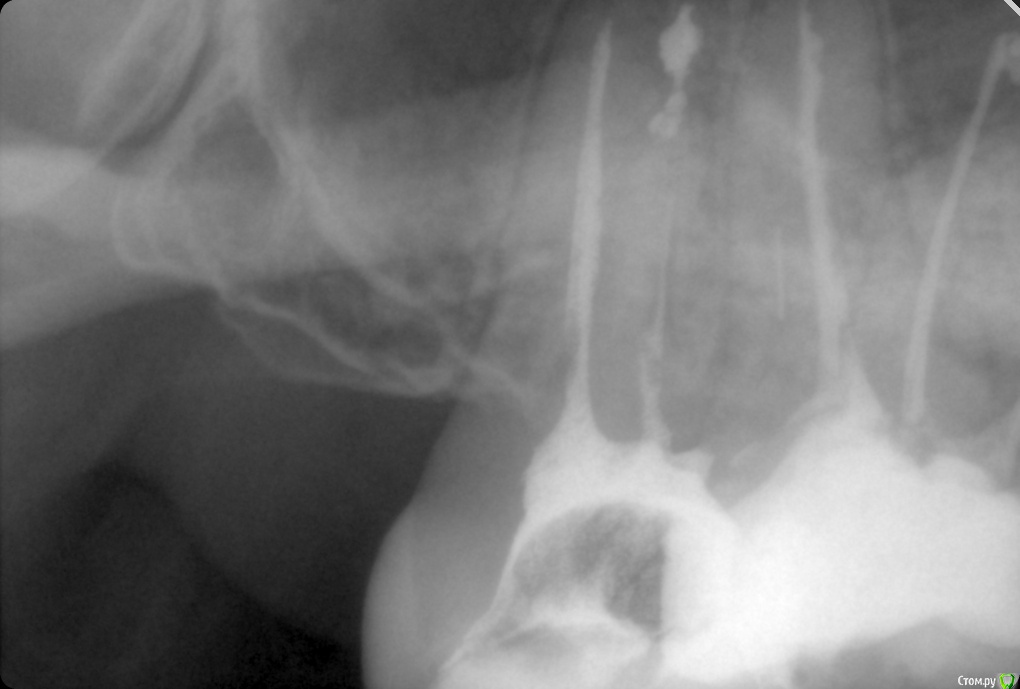

ozbourne87 Опубликовано 5 октября, 2018 Поделиться Опубликовано 5 октября, 2018 Добрый вечер! Подскажите причину боли в зубе(самый последний верхний),второй месяц лечится зуб, кальций закладывали. Пломбировали световой пломбой,потом опять болел зуб, снимали пломбу закладывали что то еще и все равно побаливает. Снимок во вложении-щас в каналах йод с каким то контрастным веществом и временной пломбой Ссылка на комментарий

shishok Опубликовано 6 октября, 2018 Поделиться Опубликовано 6 октября, 2018 А сколько каналов нашли?Мне одной кажется,что медиальный щечный канал пустой? Ссылка на комментарий

ozbourne87 Опубликовано 8 октября, 2018 Автор Поделиться Опубликовано 8 октября, 2018 Два канала нашли Ссылка на комментарий

ozbourne87 Опубликовано 8 октября, 2018 Автор Поделиться Опубликовано 8 октября, 2018 Прилагаю ещё пару снимков Ссылка на комментарий